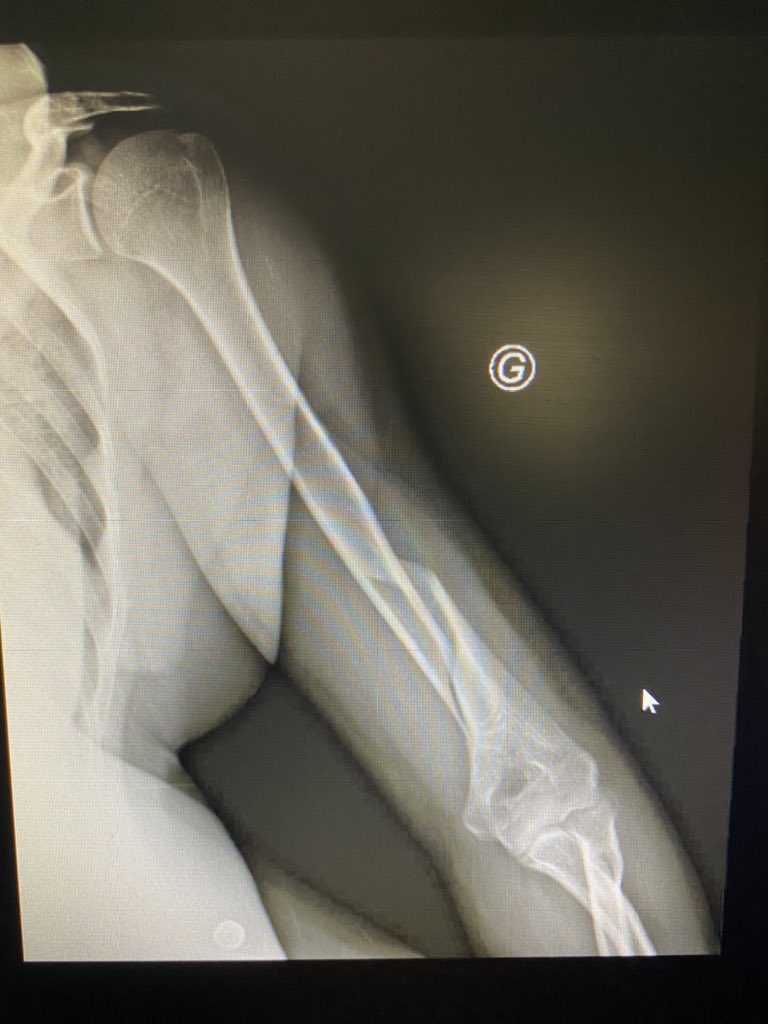

From exowmknhr.blob.core.windows.net

Bras De Fer Danger at Ramon Ratcliff blog Humerus Bras De Fer Learn about the causes, treatment, and recovery of a humeral shaft fracture, a break in the middle part of the humerus bone. En haut à l’épaule avec la scapula (anciennement omoplate), en bas au coude. The neer system divides the proximal humerus into four parts and considers not the fracture line, but the displacement as. Find out how a splint,.. Humerus Bras De Fer.